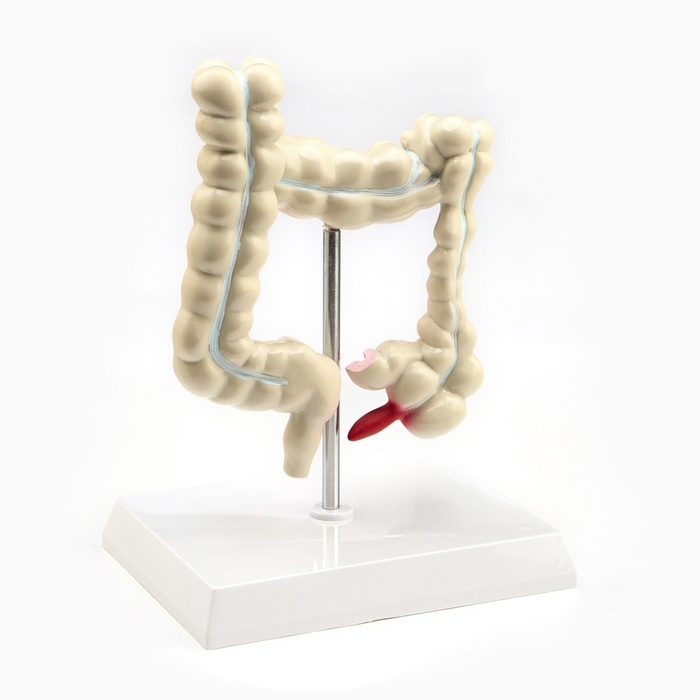

Анатомические модели

ЕКБ 39

No Brand, артикул: 7072361